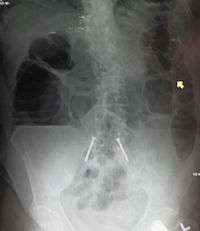

Upright abdominal X-ray demonstrating a small bowel obstruction. Note multiple air fluid levels. | |

Radiological signs of bowel obstruction include bowel distension and the presence of multiple (more than six) gas-fluid levels on supine and erect abdominal radiographs.